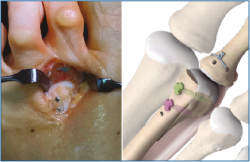

Es importante exponer el tercio proximal de F1 y cruentar en su aspecto plantar la huella de reinserción de la placa plantar, separando bien las partes blandas a este nivel, para facilitarnos posteriormente la recuperación de las suturas (Figura 4).

Figura 4. Cruentación de la huella de inserción de la placa plantar en la base de F1.

Figura 5. Distracción metatarsofalángica obteniendo un espacio de trabajo y observando perfectamente la rotura completa de la placa plantar.